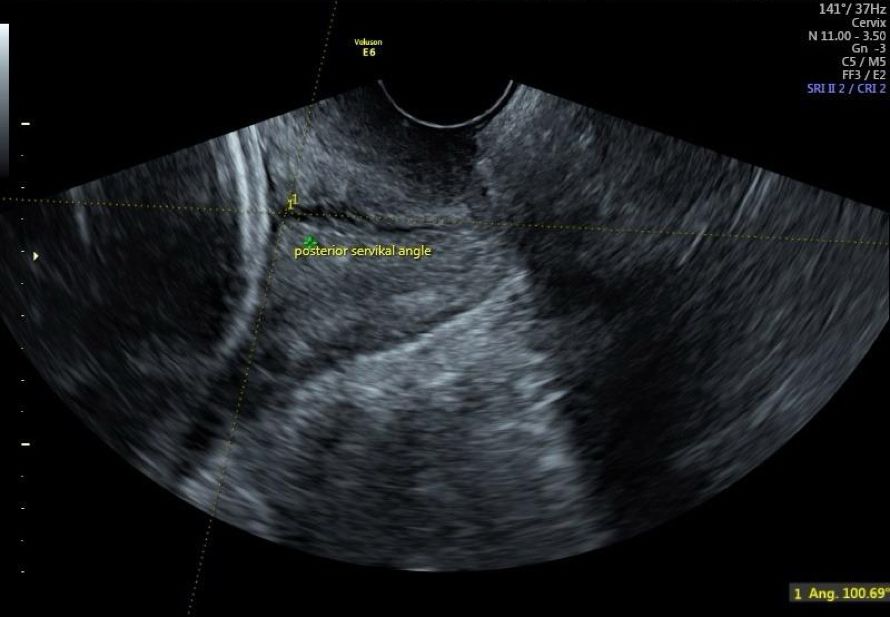

To ensure standardization of the study, measurements and examinations were performed by a single physician using the same ultrasound device (Voluson S10 BT18 5788346). First, fetal biometric measurements were taken using the transabdominal probe of the ultrasound. Then, the transvaginal probe was used to measure cervical length, uterocervical angle, and posterior cervical angle, which were recorded. Vaginal examination was performed to assess cervical dilation, effacement, and Bishop score. With the patient in the lithotomy position and empty bladder, care was taken to avoid applying pressure to the cervix with the transvaginal probe. The cervix was aligned in the midline, and the endocervical canal was visualized throughout its length. During cervical measurement, care was taken to ensure that the internal os, external os, and entire endocervical canal were visible in the same image. The distance between the external os and internal os was recorded as the cervical length. With the endocervical canal, external os, and internal os linearly displayed on the screen, the angle between the endocervical canal, anterior uterine segment, and posterior uterine segment was measured using the ultrasound's “angle measurement” feature. For the measurement of the uterocervical angle, the first line of the angle was defined along the endocervical canal used for measuring cervical length, and the second line was drawn from the internal os along the anterior uterine segment for a minimum of two centimeters. The angle between these two lines was recorded as the uterocervical angle in the form (Figure 1). When measuring the posterior cervical angle, the line extending along the endocervical canal and the line with a minimum length of two centimeters drawn between the cervix and the posterior uterine segment were taken as basis and the angle between the two was recorded as the posterior cervical angle (Figure 2).

Figure 2. Posterior cervical angle (PCA).